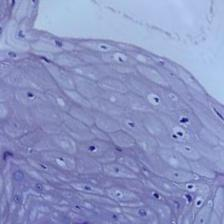

Sample Results and Metrics

Below are some sample results from the related research work demonstrating the effectiveness of augmenting database images with more features. More information can be found in papers [6, 8, 9] listed in the reference section below. In particular, the following table contains results from our paper [6].